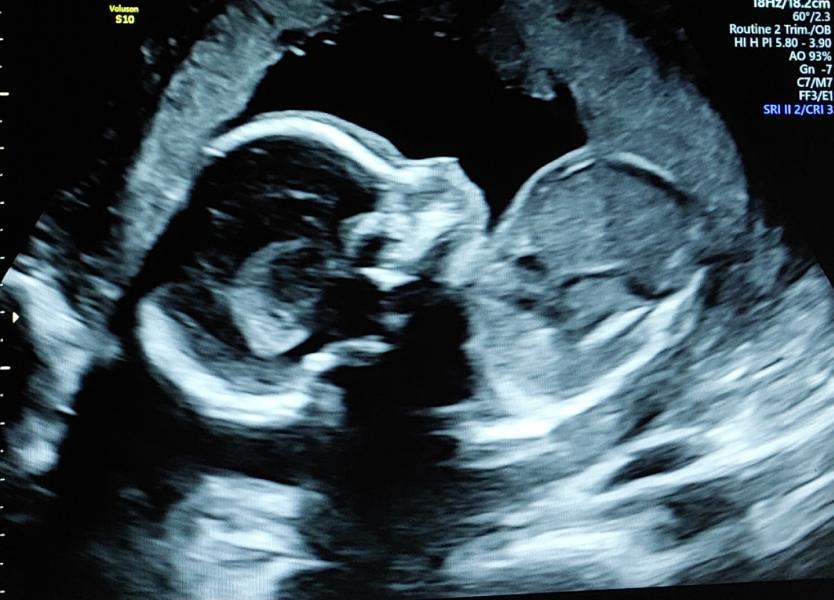

Ну вот и второй скрининг позади🙏 Я всё равно ещё не до конца осознала, что он с нами, наш долгожданный😊

Сынок в порядке, а у меня есть риски, планцента очень низко и шейка 29..ну и возраст конечно. Наблюдать каждые 2 недели.